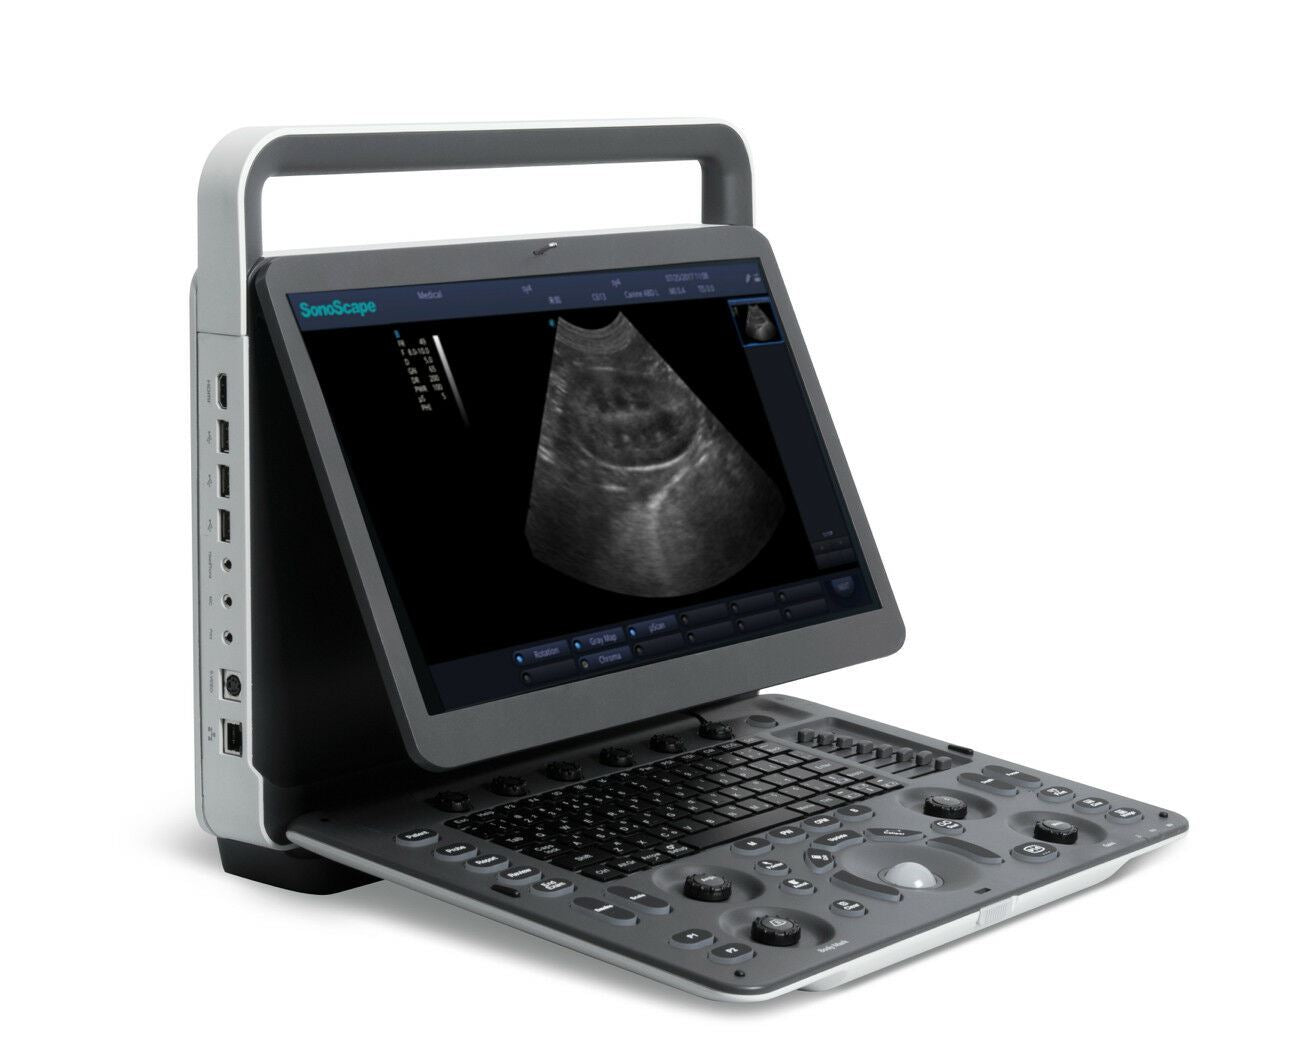

SonoScape A6V Expert (E1V) Veterinary Ultrasound - Micro Convex, Trolley, Bag

SonoScape A6V Expert (E1V) Best Veterinary Ultrasound Scanner with One Probe - Veterinary Micro Convex C613 4-13MHz for Small Animals.

The trolley as pictured is included. Warranty. Additional warranty 5% of the cost of the machine per year. Also includes carrying case, battery, and DICOM. An additional probe is $1000.

KeeboMed, Inc is the exclusive seller for SonoScape A6V Expert (E1V) for USA and Canada market.

- Improved image quality, 40% better than A6V

- 16MHz Transducer frequency is higher than A6V for all probes. The rectal probe also has a higher frequency but still continues to have a 70mm lens.

- A larger, more user-friendly 15" LED screen, but is even more lightweight than A6V.

Sonoscape A6V Expert (E1V) is the best black and white veterinary ultrasound that can be found on the market today. Image quality is far ahead than other brands. Super large image area with an anti-glare screen. Clear image under the sunshine, especially for veterinary and field application.

- 15.6”High-Resolution LCD Color Monitor